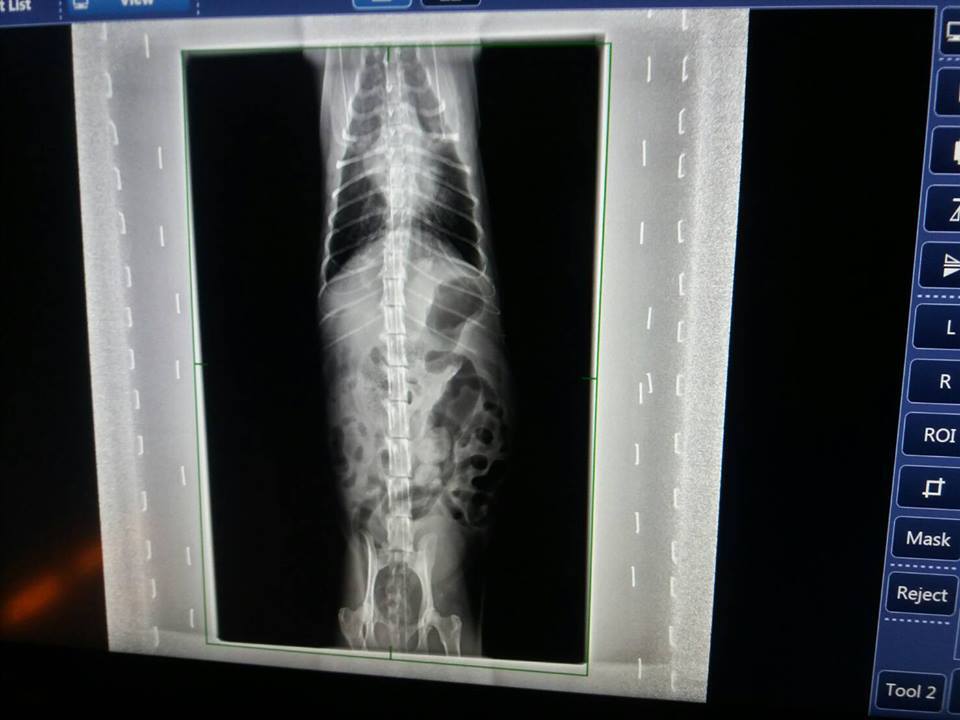

---X光

X光下比較一個月前肺部團塊霧點,

本次已有更清澈,

左側原先擔心是否纖維化的地方,本次有再度散掉一些

右側於上月狀況即有明顯變清澈,本次也有在更改善一些

整體肺部狀況好轉很多